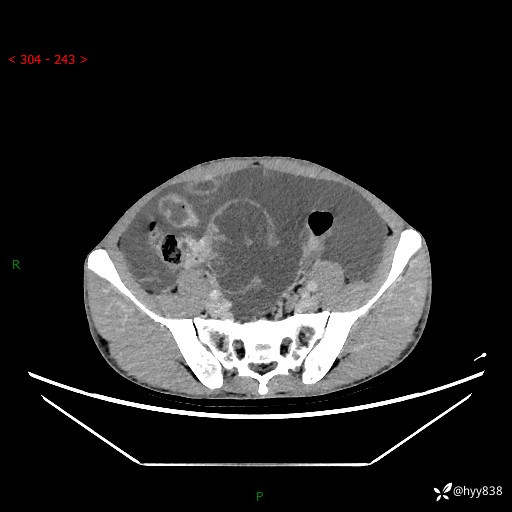

现病史:患者10天前无明显诱因出现腹部胀痛不适,无畏寒发热,无胸痛胸闷,无心慌气短,无恶心呕吐,无腹泻及黑便,无粘液血便及里急后重等症状,4天前在当地县人民医院就诊,行腹部CT示:下腹部占位性病变,腹腔及盆腔积液;今患者为求进一步诊治来我院治疗,门诊以“腹水”收治入院。 发病以来,精神饮食可,大小便正常,体重体力无明显变化。

腹部CT平扫+增强